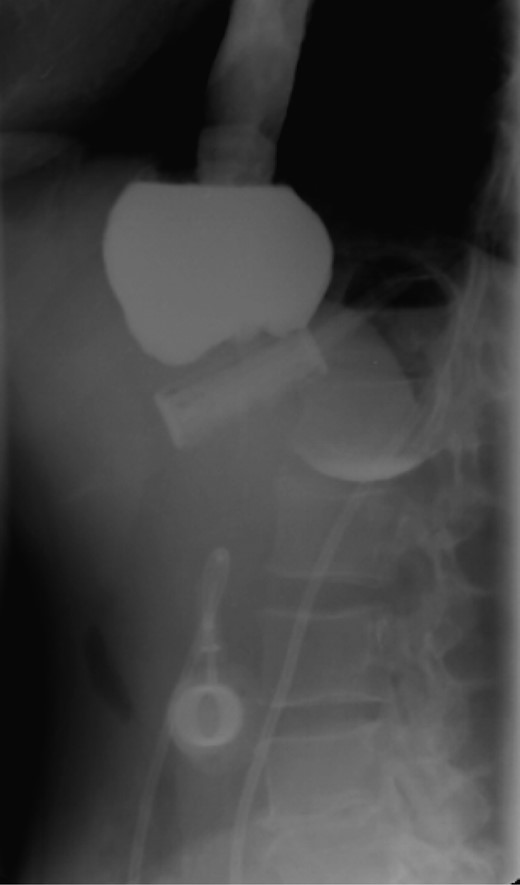

On the first day of admission, gastric banding was completely deflated. Rx abdomen showed posterior slippage of the ring (Fig. 1). Subsequently, the patient underwent rehydration therapy, 20-day total parenteral nutrition and infusion of human albumin. During that period, we examined her upper digestive tract with oral water-soluble contrast (Fig. 2) with the result of a thin liquid passage downstream of the ring and marked gastric pouch distension. Esofagogastroscopy was performed, which was negative for erosion or gastric perforation; however, it revealed a 1-cm-diameter passage through the gastric band. Despite an improvement in symptoms with partial resumption of semi-liquid intake, the patient continued to experience nausea and vomiting. For this reason, she underwent laparoscopic removal of gastric banding. In the operating room, she was placed in the lithotomy position; we placed a 10-mm optical trocar in supraumbilical region, a 5-mm one in the right upper quadrant and a 10-mm one in left upper quadrant near the subcutaneous tank. After lysis of adhesions between liver and stomach, the intraoperative picture showed a banding displacement, confirming posterior slippage of the banding and its sliding back to the level of previous gastro-jejunal anastomosis. Ascitic effusion due to dysproteinemia was reported. A methylene blue test showed no gastric perforation. After this procedure, the patient started to resume liquid intake in the first postoperative day and food intake in the second postoperative day, with complete resolution of vomiting and nausea. Then, she was discharged with the advice of an appropriate diet and invited to attend a recall visit 10 days later. In subsequent follow-up, the complete resolution of clinical symptoms was confirmed together with an improvement of the biohumoral picture.